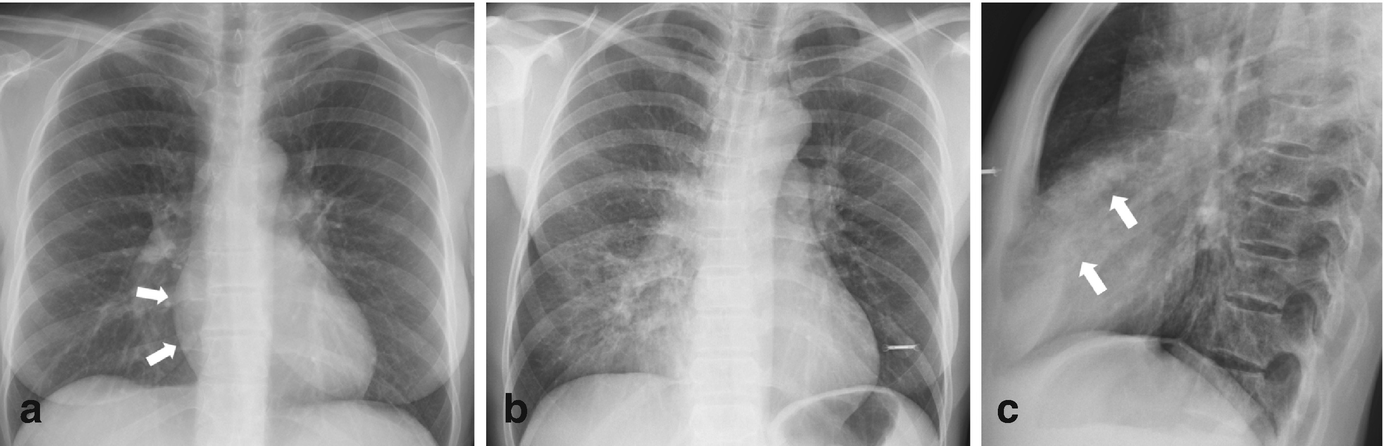

CXR PA and Lateral shows bilateral and extensive reticular nodular changes slightly more prominent in the upper lung zones. A reticulonodular interstitial pattern is an imaging descriptive term that can be used in thoracic radiographs or CT scans when are there is an overlap of reticular shadows with nodular shadows. LANGERHANS HISTIOCYTOSIS RETICULONODULAR PATTERN 53-year-old female with nicotine dependence presents with dyspnea and cough.

Diagnosis is frequently delayed and prognosis is usually poor. Respiratory Bronchiolitis-Associated Interstitial Lung Disease. The reticular pattern consists of a network of linear densities Fig.

This may be used to describe a regional pattern or a diffuse pattern throughout the lungs. While this is a relatively common appearance on a chest radiograph very few diseases are confirmed to show this pattern pathologically. A reticulonodular interstitial pattern is an imaging descriptive term that can be used in thoracic radiographs or CT scans when are there is an overlap of reticular shadows with nodular shadows.

Click to see full answer. This may be used to describe a regional pattern or a diffuse pattern throughout the lungs.